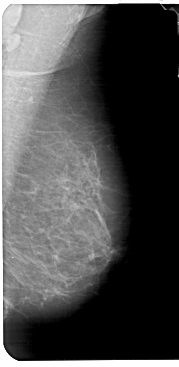

A_1776_1.RIGHT_CC

RIGHT_CC LINES 5236 PIXELS_PER_LINE 2446 BITS_PER_PIXEL 12 RESOLUTION 43.5 NON_OVERLAY